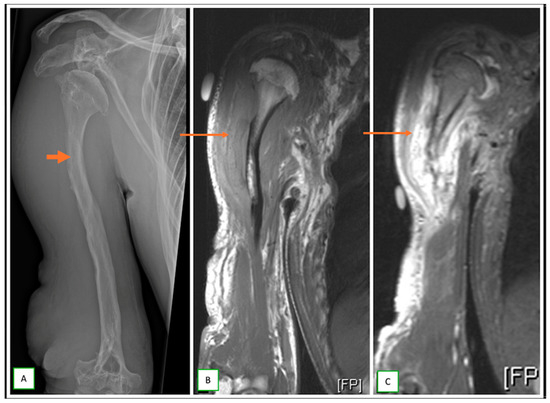

- Primary Sarcomas: Soft-tissue sarcomas are uncommon, accounting for just over 1% of adult malignancies. Synovial sarcoma, clear cell sarcoma, and epithelioid sarcomas are known to involve peripheral nerves. CT/MR reveals a large soft tissue mass with areas of necrosis or calcification and heterogeneous contrast enhancement. F-18 FDG uptake is useful for both tumor staging and treatment assessment (Figure 26, Figure 27 and Figure 28).